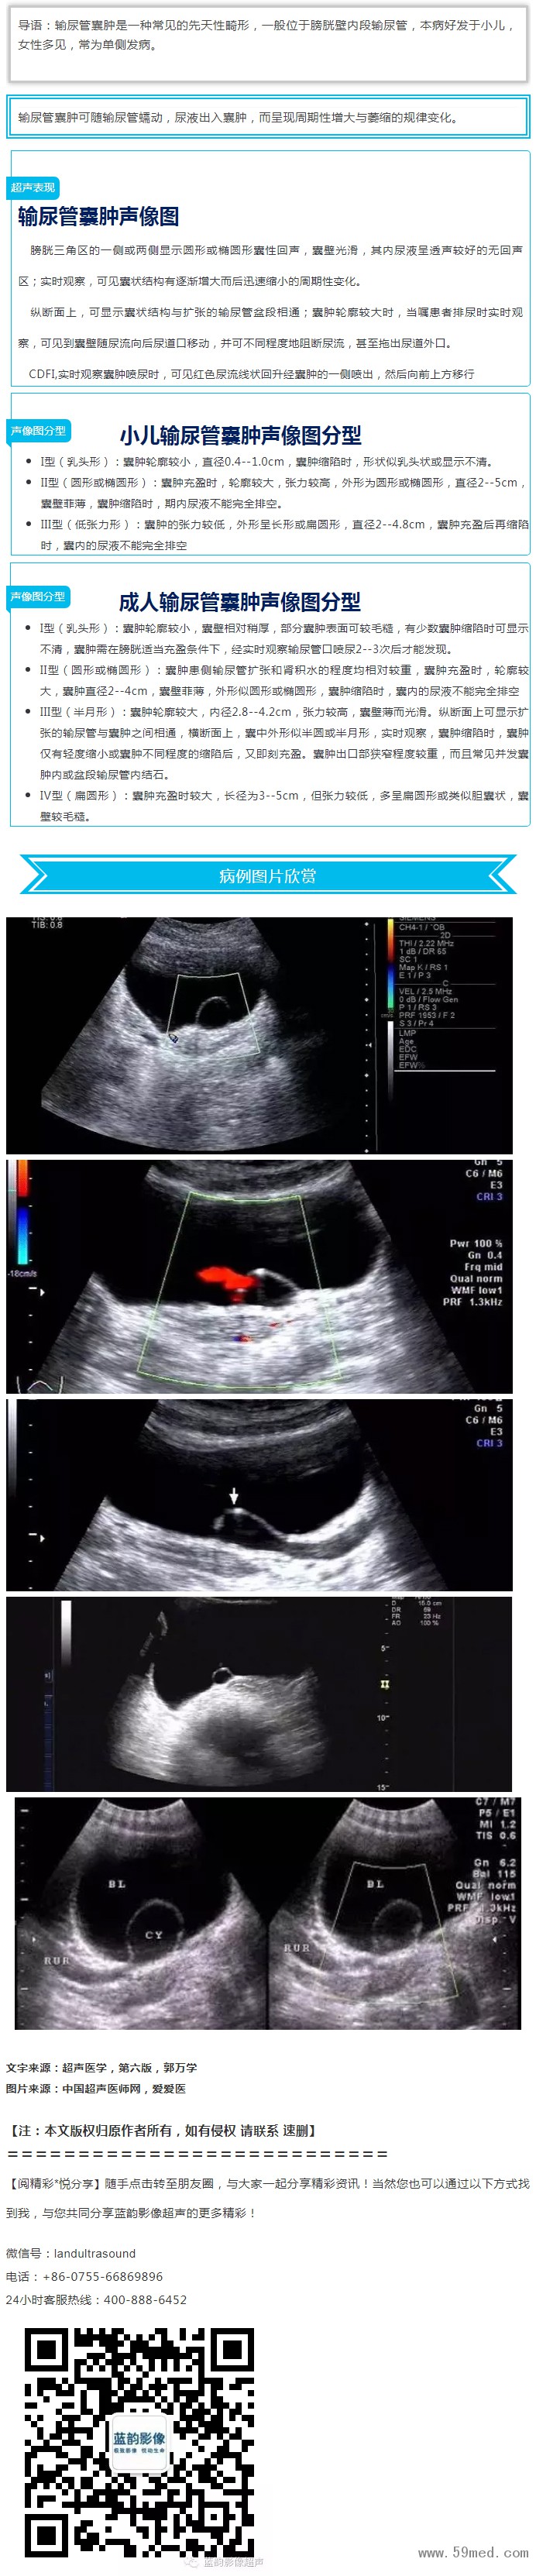

【超聲微課堂】輸尿管開口囊腫的超聲診斷